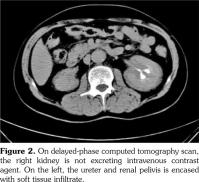

A 51-year-old male patient admitted to our outpatient clinic with complaints of flank pain and fatigue. He had a history of renal stones and peripheral arterial disease. He had a medically unmanageable hypertension. Blood pressure was 200/110 mmHg. Serum creatinine level was 1.2 mg/dL. He was evaluated with contrast- enhanced multislice computed tomography. Along with small calyceal stones, there was bilateral, quite symmetrical perinephric ''rind-like'' soft tissue infiltration. Right kidney was atrophic but still functioning without pelvicalyceal contrast excretion. The soft tissue infiltration obliterated both renal hila and caused proximal ureteral stenoses with mild calyceal dilation on the left side (Figures 1 and 2). Distally, the ureters were normal. Incidentally, abdominal aorta, common iliac arteries, proximal celiac trunk, and proximal renal arteries were noticed to appear “coated” with subtle perivascular tissue infiltration. An endovascular aortoiliac stent-graft was in place. He rejected any further diagnostic intervention after he presented with a blood creatinine of 2.2 mg/dL. He underwent an unenhanced computed tomography examination with the same findings before. Renal scintigraphy revealed a non-functioning right kidney. Perinephric soft tissue infiltration was considered as the differential diagnosis of ECD. Direct radiographies of the extremities were obtained. All of the long tubular bones showed diametaphyseal cortical and patchy medullary sclerosis reinforcing the diagnosis of ECD (Figure 3). The patient underwent right nephrectomy for the control of hypertension and a double-J stent was placed on the left side for the relief of ureteral obstruction. The nephrectomy specimen showed the typical histological features of ECD. Serum creatinine level dropped to the borderline values after the operation and his blood pressure was in the normal range with medications. The pathological analysis of the nephrectomy specimen revealed an inflammatory infiltrate formed by foamy histiocytes that were positively stained for CD68 and neutrophilic aggregates which confirmed the preoperative diagnosis (Figures 4 and 5). A written informed consent was obtained from the patient.

The histiocytic infiltrative process, as found in our case, may involve the retroperitoneum in approximately 29 to 68% of patients.(4,5) The soft tissue infiltrate around the aorta and its major branches can be misdiagnosed as arteritis, lymphoma or retroperitoneal fibrosis.(4) The process may lead to severe arterial stenosis and the consequences include cerebral ischemia, cardiac angina, mesenteric ischemia, or renovascular hypertension.(6-8) Adrenal glands, kidneys, renal arteries, ureters, and adjacent anatomical spaces may be involved in the process. Infiltration of perirenal space may extend to the pararenal space with irregular borders, thus will be given the name “hairy kidney”.(6) Extension to the renal sinuses and pedicles, proximal and distal ureters is possible and may cause obstruction and eventually, as in our case, compromise renal function.(8-10)

In our case, computed tomography findings suggested retroperitoneal fibrosis but the infiltrate did not involve the vena cava and the paraaortic infiltration was circumferential instead of sparing the posterior aspect of the aorta. Also, the perinephric infiltration was far more striking than the perivascular space which is inconsistent with retroperitoneal fibrosis. Therefore, the differential diagnosis consisted mainly of processes involving perinephric and perivascular spaces, namely, lymphoma, retroperitoneal fibrosis, and ECD. The diagnosis of ECD was strongly suggested with the radiographic findings of the extremities which revealed symmetrical dia-metaphyseal osteosclerosis.